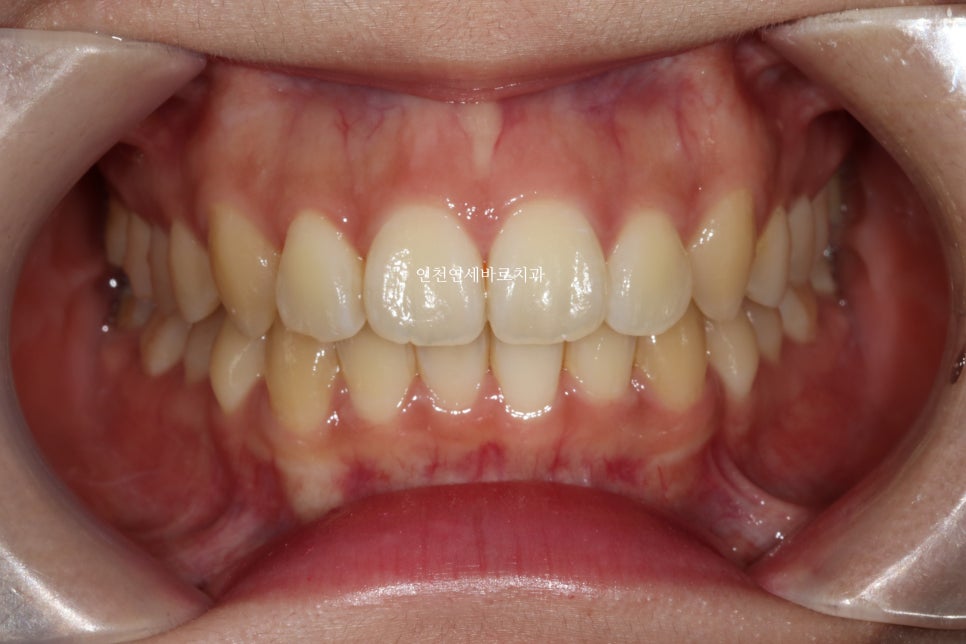

지난 주 왔을때의 모습입니다. 역시 잘 유지되고 있습니다.

긴밀한 교합과 배열로 잘 유지되고 있다고 판단됩니다.

교정 치료는 당장 1-2년의 배열뿐만 아니라, 그 이후의 장기 유지 관리도 매우 중요합니다.